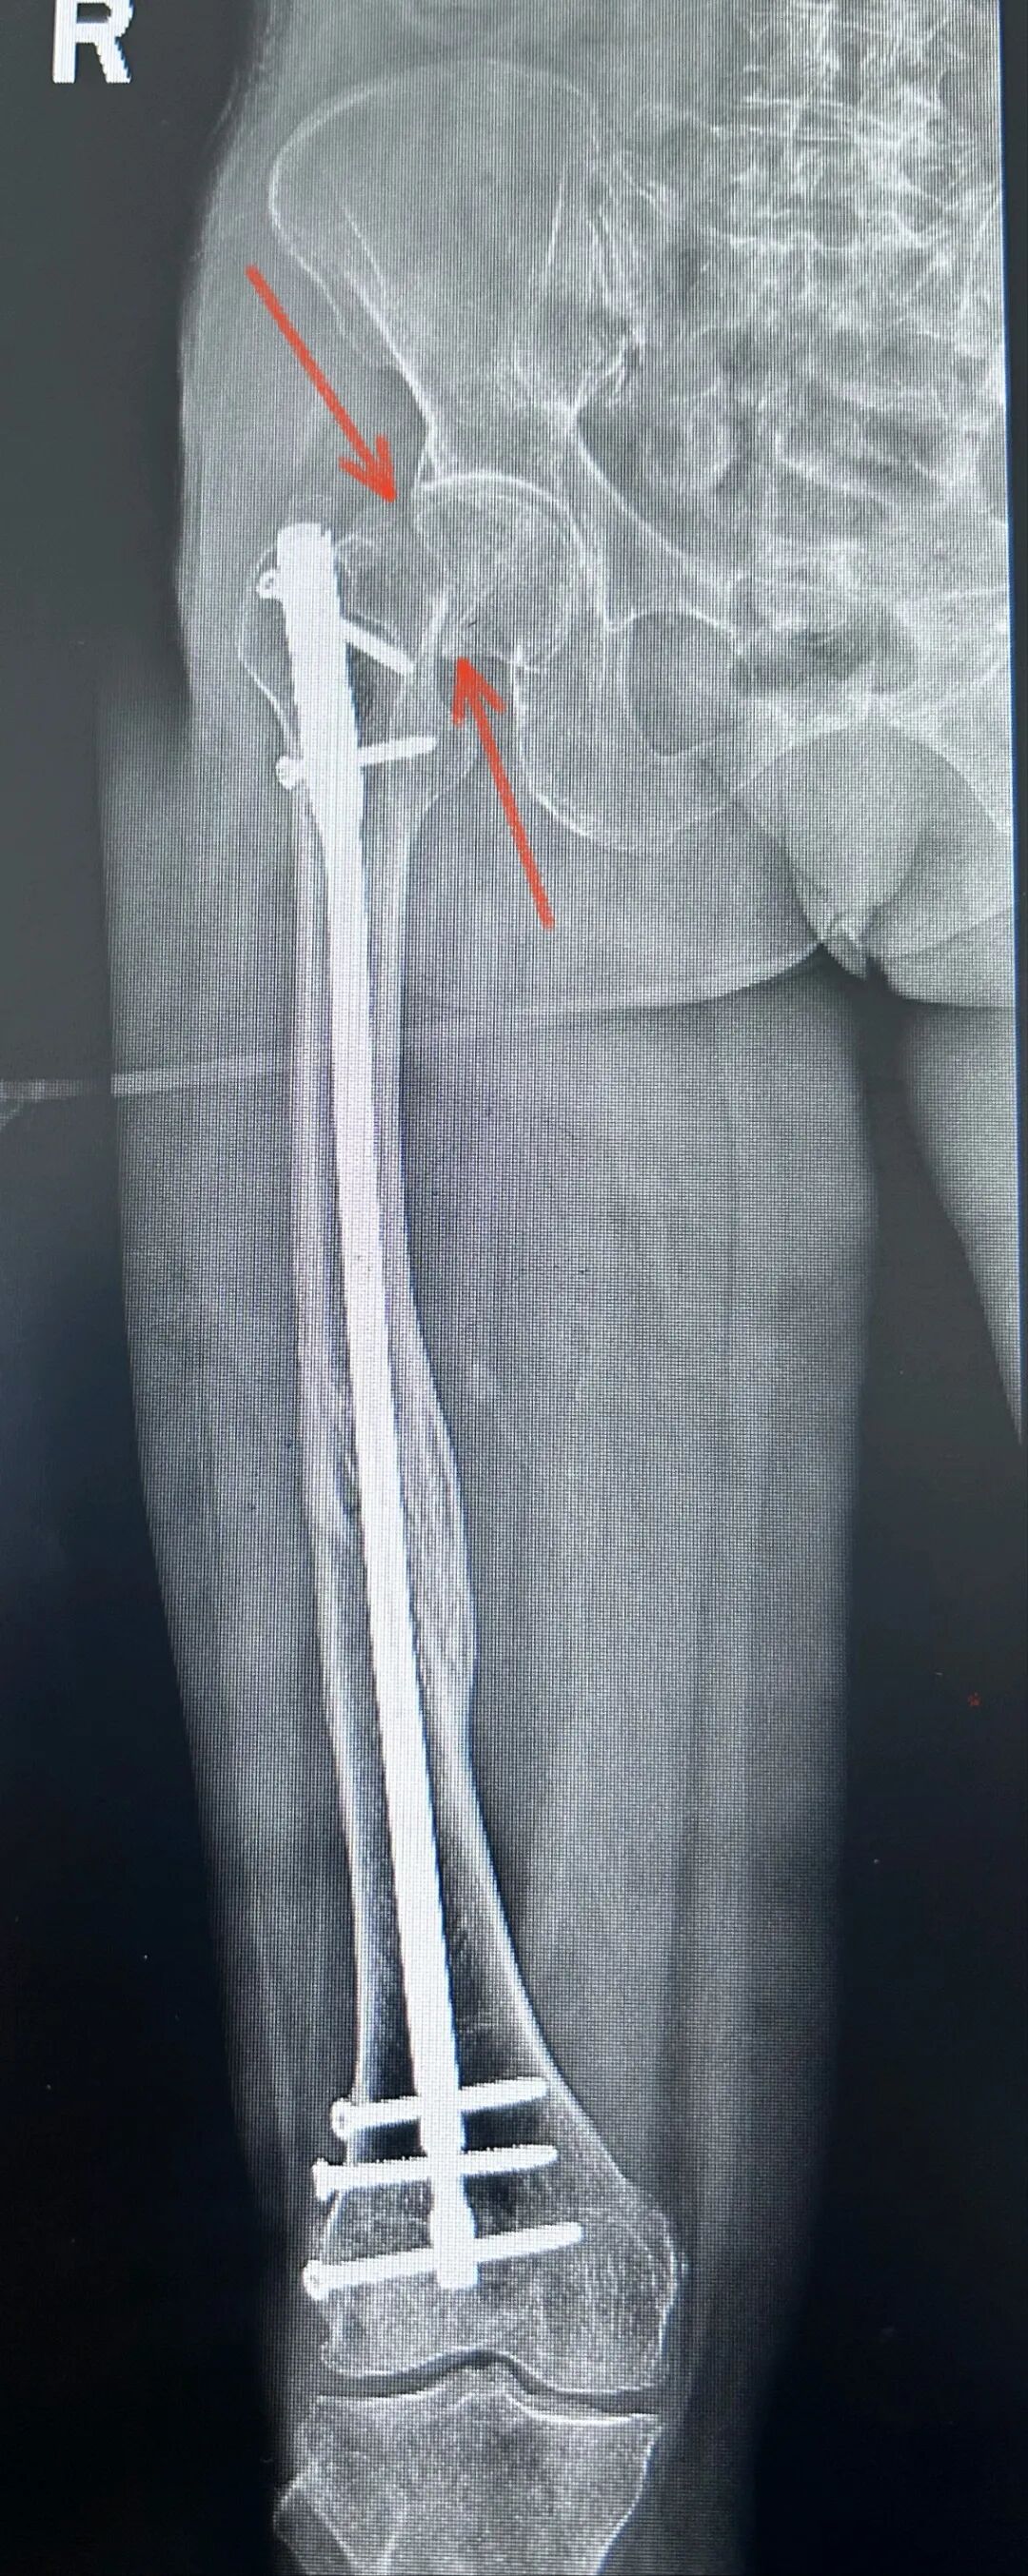

病例一:

26岁,男性,骨质非常好

初次手术主刀选择了

1,逆行髓内钉

2,切开复位

单从片子上看

手术做的也挺好

复位也好

钉子长度也好

再来分析下失败原因

1,能顺行不逆行,选择了逆行

2,能闭合不切开,选择了切开

当然再骨折的原因

大概率是近端锁钉锁不准

打孔次数过多的原因

但是青壮年逆行髓内钉

再次受到暴力

仍旧避免不了

转子下,股骨颈骨折的风险